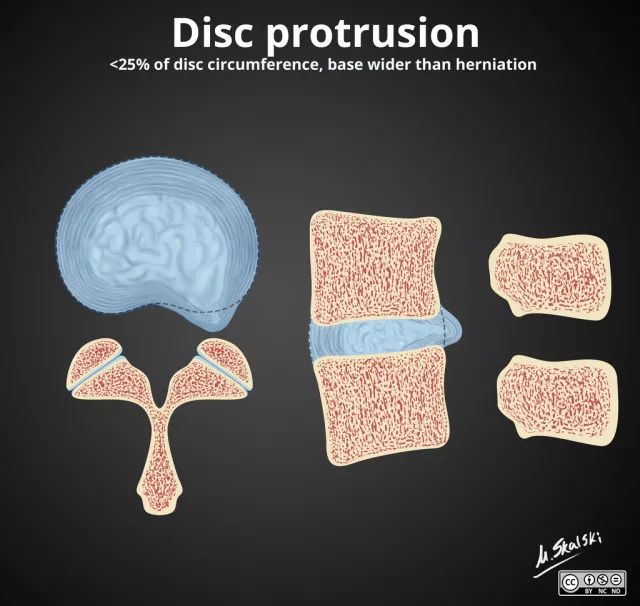

2. 椎间盘突出(Disc protrusion)

为髓核突入纤维环内但后纵韧带未破裂,表现为椎间盘局限性向椎管内突出。

图 4 椎间盘突出的影像学定义为突出部分小于椎间盘边缘的25%,并且基底部>突出部分的直径;突出椎间盘的两边与髓核的中心的夹角<90°